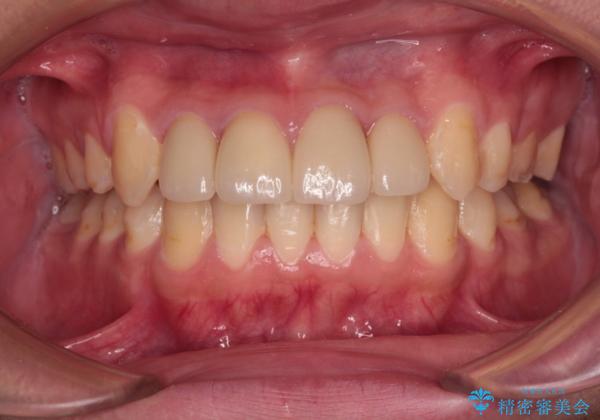

矯正治療後は上顎前歯4本をオールセラミッククラウンにて補綴治療を行うこととしました。

むし歯が多かったため、ワイヤー矯正中に処置したむし歯が悪化することが懸念されましたが、歯磨きをしっかりと行ってくれたため、とても良好な状態を維持することができました。